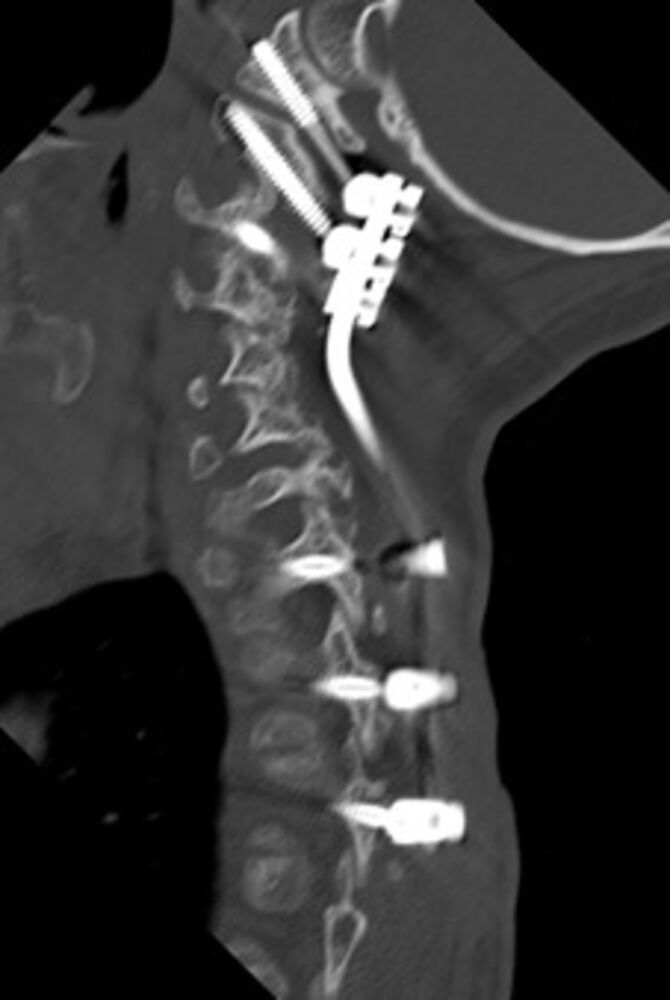

- Versteifungsoperationen bei Instabilitäten und Fehlstellungen wie degenerativer Skoliose, Wirbelgleiten, Myelopathie

- Stabilisierungs- und Dekompressionsoperationen bei Rheuma, Brüchen und Verletzungen (Wirbelbrüche, Wirbelverrenkungen)

Seit 2017 führen wir unsere Stabilisierungs- und Versteifungsoperationen mit einem intraoperativen CT (s.o. AIRO©, Fa. Brainlab) durch. Diese intraoperative Computertomographie liefert direkt im Operationssaal während des Eingriffs hochauflösende Bilder von der Wirbelsäule. Zusammen mit einer Navigationssoftware wird ein dreidimensionaler Plan der entsprechenden Körperregion erzeugt. Mit Hilfe der Bildgebung können wir die notwendigen OP-Schritte plangerecht umsetzen und z.B. Implantate mit sehr hoher Präzision einsetzen. Gerade bei komplizierten Eingriffen an der Wirbelsäule hilft die neue OP-Technik, Patienten sicher und schonend zu therapieren. Die intraoperative Bildgebung, direkt im OP, erlaubt komplexe Operationen genauer und sicherer durchzuführen und dem Operateur noch während der Operation das Ergebnis zu überprüfen und bei Bedarf zu optimieren. Belastende Folgeoperationen sind so deutlich seltener und die Behandlungsqualität und Sicherheit für Patienten dadurch erheblich verbessert.